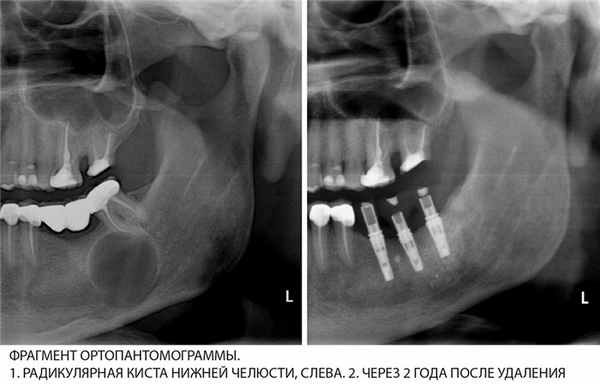

Резидуальные (остаточные) кисты возникают, когда, например, после удаления корня зуба на месте экстракции остается небольшой остаток или когда врач допускает ошибку во время лечения. Чтобы локализовать его, организм ограничивает область воспаления. В области, где был удален зуб, образуется гранулема. Остаточная киста полностью видна на снимке. Диаметр кисты составляет от нескольких миллиметров до сантиметра и более.

Иногда после удаления зуба с кистой, оболочку которой не удалили, остаются резидуальные (остаточные) кисты, которые могут начать расти, как обычные кисты. Рентгенодиагностика помогает обнаружить их, после чего решается вопрос об их удалении с помощью одного из вышеперечисленных методов.